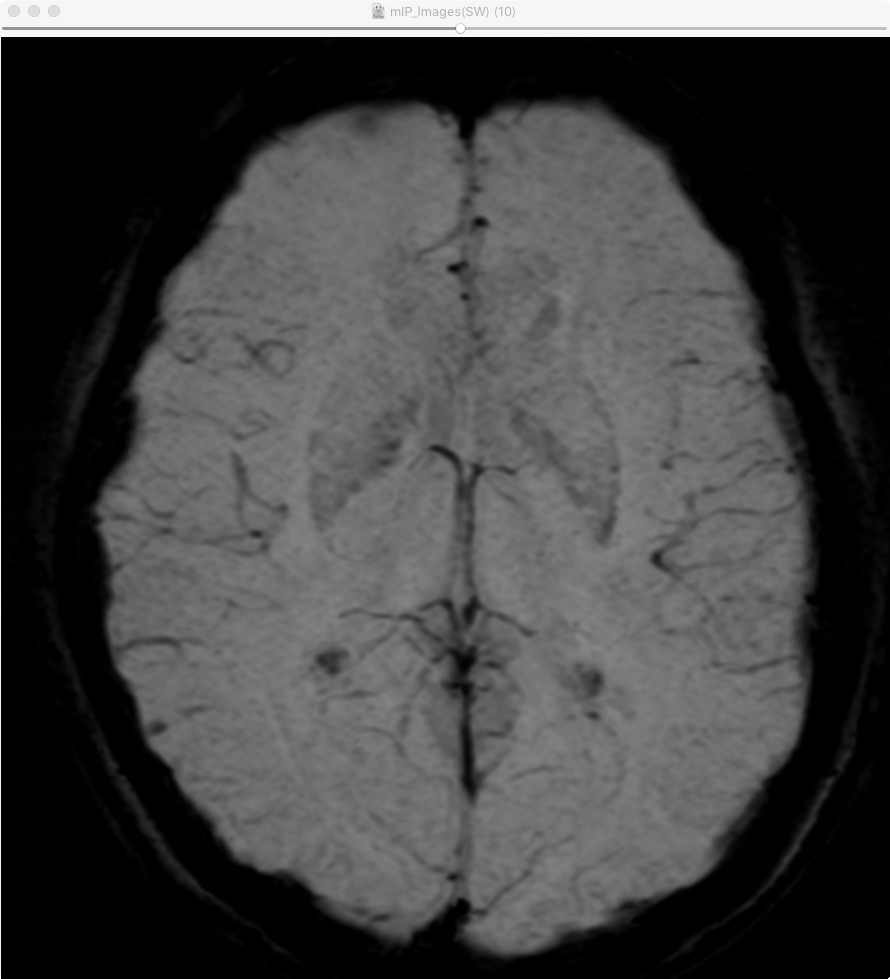

画像サンプル |

---|